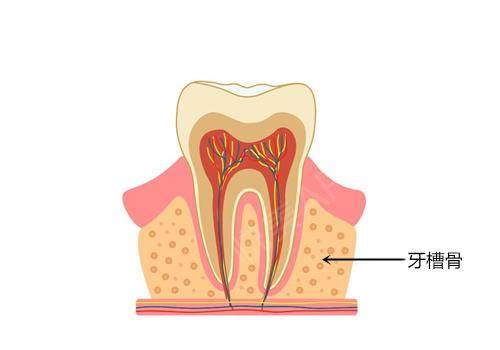

一、缺牙困境:超薄牙槽骨患者的隐痛

“缺牙十年,每次张嘴都像在展示‘年轮’。”35岁的李女士因牙周病导致上颌前牙区牙槽骨高度仅剩4.5mm,传统种植体因长度不足无法植入。这种因牙槽骨萎缩导致的种植难题,在临床中占比高达30%。

超薄牙槽骨患者常面临三重困境:

传统种植体适配性差:常规种植体长度普遍在8mm以上,而牙槽骨高度不足6mm时,强行植入易穿透上颌窦或损伤神经管;

骨水平稳定:边缘骨吸收量平均0.3mm,远低于海内外标准1.5mm;